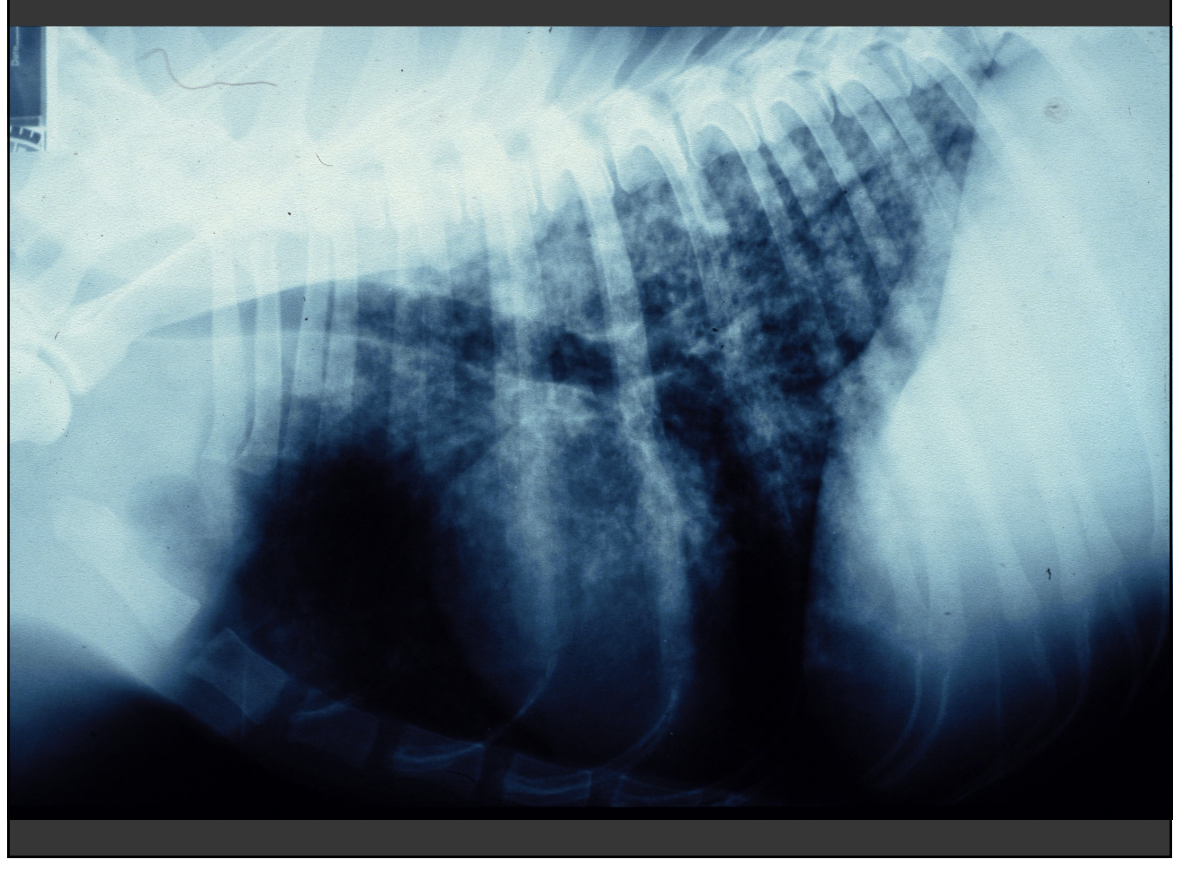

chest xray in canine lymphoma

Lat and DV sufficient

• Lymph node enlargement – cranial mediastinal, suprasternal, tracheobronchial nodes and thymus

• Pulmonary infiltration – variable appearance, difficult to differentiate from age change – micronodular interstitial pattern

• Pleural effusion

• consider comorbidity

<p>Lat and DV sufficient </p><ul><li><p>Lymph node enlargement – cranial mediastinal, suprasternal, tracheobronchial nodes and thymus </p></li><li><p>Pulmonary infiltration – variable appearance, difficult to differentiate from age change – micronodular interstitial pattern </p></li><li><p>Pleural effusion </p></li><li><p>consider comorbidity</p></li></ul><p></p>

Diagnostic Imaging: AXR

• Internal lymph node enlargement – medial iliac (sublumbar) lymphadenopathy – (mesenteric lymphadenopathy) • Hepatosplenomegaly • Peritoneal effusion • Concurrent disease